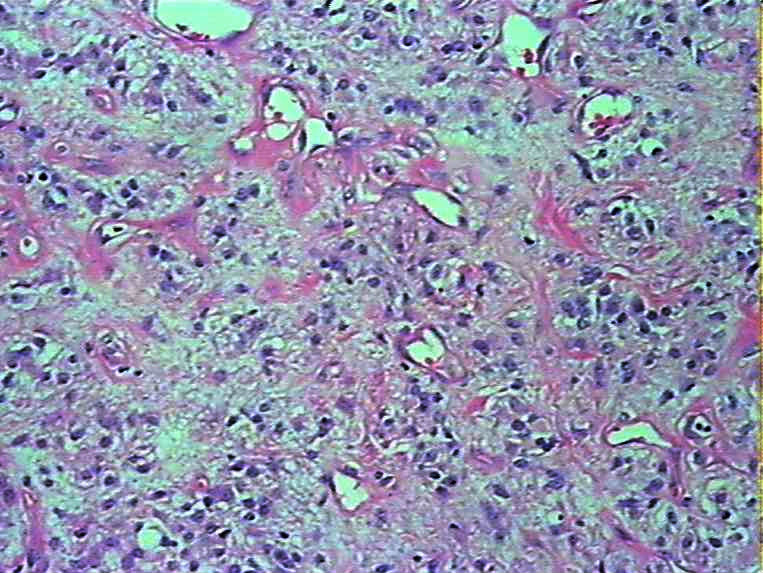

腹部肿物会诊血管球瘤

女45发现下腹部皮下肿物4个月

灰白色肿物一枚,9*8*5cm,切面实性、质韧,似有包膜

参考诊断

血管球瘤

会诊血管球瘤